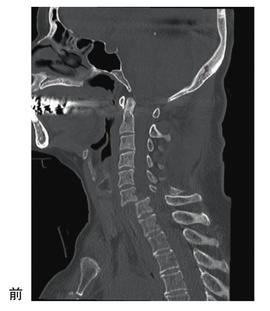

第60回 午前 作業療法士実地問題

科目:

大分類: 脊髄損傷

64歳の男性。バイク走行中に転倒し、救命救急センターへ搬入された。救急外来到着時の頸椎単純CTを別に示す。頸椎脱臼骨折と診断され、同日手術が施行された。術後、四肢麻痺と肛門周囲の感覚脱失を認め、Zancolliの四肢麻痺上肢機能分類C6B1完全麻痺の頸髄損傷と診断された。目標として設定する動作で最も適切なのはどれか。

_sfC2_AbwV

1

起き上がり動作

2

屋内平地での車椅子駆動

3

電動車椅子を用いた移動

4

側方アプローチの移乗動作

5

床から車椅子への移乗動作